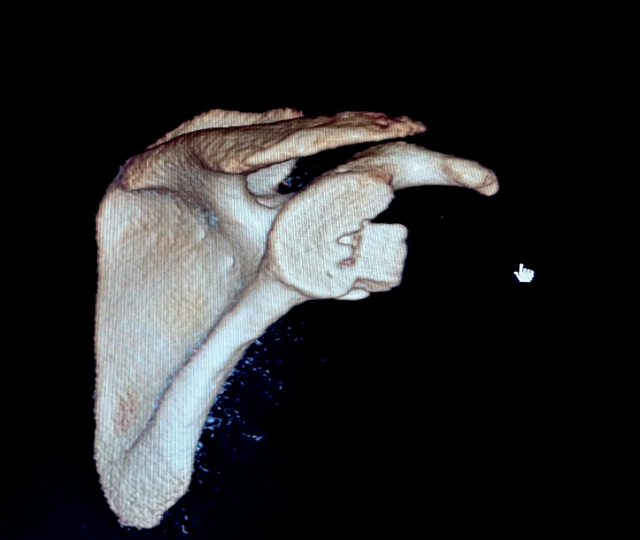

术中图片

对涵涵的病情进行充分评估后,暴丁溯副教授团队决定为涵涵实施关节镜下肩关节复发性脱位+肩袖损伤翻修手术,采取游离髂骨移植技术修复关节盂骨缺损,后期经过中西医结合康复治疗,涵涵的肩关节功能逐渐恢复。出院之际,涵涵和家长特意送来了锦旗表示感谢。此后,涵涵的肩关节未再出现脱位的情况。